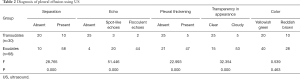

The regression equations for the pleural effusion <500 mL group (F=0.142, P=0.988) and the >1,000 mL group (F=1.533, P=0.212) showed no statistical significance. Only the regression equation of the group with a pleural effusion amount of 500–1,000 mL in the sitting position had statistical significance (F=4.866, P=0.001; Table 3).

Full table

The t-test for each regression coefficient showed that the P values for maximum depths at the subscapular line (X1) (t=3.810, P=0.001) and midclavicular line (X5) (t=–2.061, P=0.046) and the maximum thickness at the subscapular line (X6) (t=2.827, P=0.008) were all less than 0.05 and could therefore be used as independent variables in MLRM using the following equation:

According to the standardized residuals histogram, the standardized residuals of these measurements were normally distributed (Figure 2). According to the normal P-P plot of regression standardized residual, the points in the graph were basically located in one straight line. Thus, the equation was proven to be statistically significant (Figure 3).

The pleural effusion drainage amount could be estimated in accordance with the maximum depth of pleural effusion measured at the subscapular line and the maximum thickness measured at the subscapular line by US.

In the 44 patients with a pleural effusion amount of 500–1,000 mL, the agreement rate of the pleural effusion drainage amount was 84.1% (37/44).

The regression equations for the pleural effusion with exudate and transudate are shown in Table 4.

Full table

Binary logistic regression analysis was performed with exudates and transudates as the dependent variables and the above characteristics as the independent variables, and the results are shown in Table 4. Pleural thickening, transparency, and echo can be used as independent variables to establish the model (P=0.034), and the equation for the model was as follows: